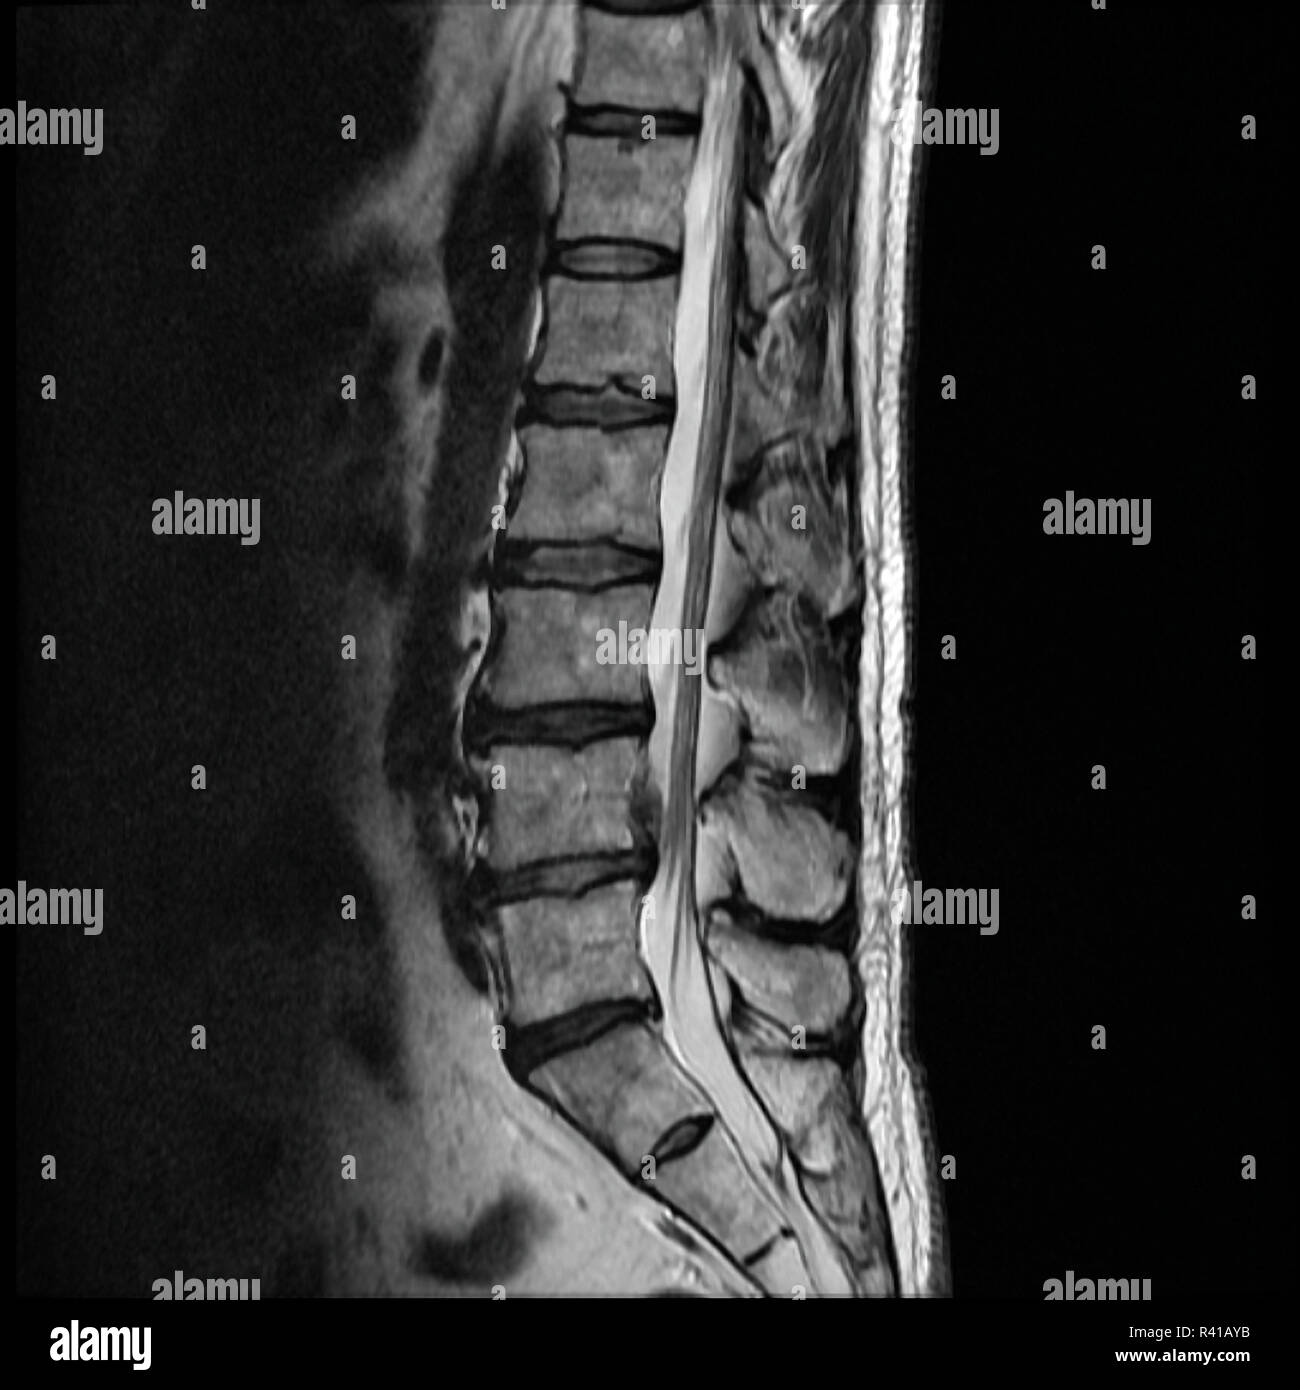

From www.alamy.com

Herniated lumbar disc hires stock photography and images Alamy Lumbar Hernia Reddit In these cases, doctors usually follow a pattern of treatment. I got diagnosed with 3 herniated discs in my lumbar spine and lumbar degenerative disc disease. I had to lie to my doctor to get an mri after seeing. A herniated disc tends to heal gradually and usually progresses through stages, each with its own characteristics and challenges. I herniated. Lumbar Hernia Reddit.